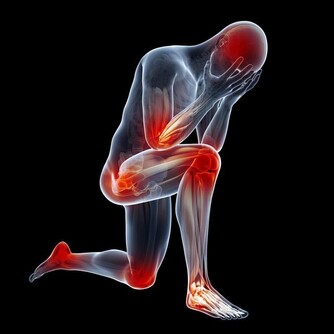

糖尿病是健康的無形殺手 糖尿病是健康的無形殺手,除了家族遺傳糖尿病外,台灣人飲食日漸西化、外食人口越來越多,又缺乏運動,不知不覺中造就了肥胖身材,糖尿病也會悄悄上身! 人只要一肥胖,就會產生胰島素阻抗,胰島素分泌的品質會變差,但為了維持血糖平衡,胰臟就得不斷加倍做工分泌胰島素,最後日漸衰退,再也無法分泌足夠的胰島素,血液中的血糖會因此上升,糖尿病就來報到了。 典型症狀: 多喝、多吃、多尿、體重減輕 很多糖尿病是吃出來的!近10年來,因飲食引起的糖尿病年齡有逐漸下降的趨勢。台北榮總新陳代謝科主治醫師石光中表示,現在門診中偶爾可看到11、12歲的糖尿病患,主要因為青少年偏好高熱量飲食,愛吃炸雞、薯條等油炸食物,也愛吃蛋糕、喝含糖飲料等甜食或糖化食物,還有在電腦前久坐、少運動,造成過度肥胖,因而年輕小胖子得到第2型糖尿病的人數是第1型的6倍之多。